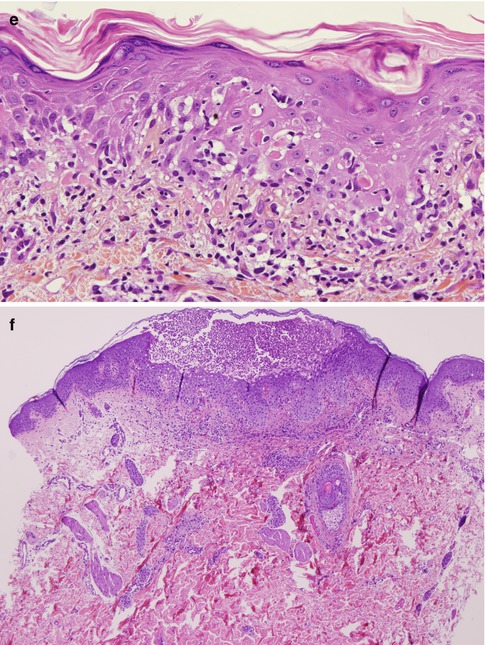

Fig. 16.4

(a) Pemphigus vulgaris, DIF for IgG. Direct immunofluorescence examination of the skin showing deposition of IgG on the cell surface of epidermal keratinocytes. A suprabasal intraepidermal blister can also be observed (original magnification ×200). (b) Pemphigus vulgaris, DIF for C3. Direct immunofluorescence examination of the skin from the same patient as in (a) showing deposition of C3 on the cell surface of epidermal keratinocytes of the lower epidermis. A suprabasal intraepidermal blister can also be observed (original magnification ×200). (c) Pemphigus foliaceus, DIF for IgG. Direct immunofluorescence examination of the skin showing deposition of IgG on the cell surface of epidermal keratinocytes of all the epidermis (original magnification ×200). (d) Pemphigus foliaceus, DIF for C3. Direct immunofluorescence examination of the skin from the same patient as in (d) showing deposition of C3 on the cell surface of epidermal keratinocytes of the lower epidermis. These deposits are less intense than the IgG deposits (original magnification ×200). (e) Paraneoplastic pemphigus, DIF for IgG. Direct immunofluorescence examination showing deposition of IgG on the cell surface of epidermal keratinocytes. This pattern is indistinguishable from other types of pemphigus (original magnification ×400). (f) Paraneoplastic pemphigus, DIF for C3. Direct immunofluorescence examination showing granular deposits of C3 along the basement membrane zone. This feature can be suggestive of paraneoplastic pemphigus, but can also be seen in other types of pemphigus (original magnification ×100). (g) IgA pemphigus, DIF for IgA. Direct immunofluorescence examination showing deposition of IgA on the cell surface of epidermal keratinocytes from the upper half of the epidermis (original magnification ×100). (h) IgA pemphigus, DIF for C3. Direct immunofluorescence examination from the same patient as in (g) showing negative staining for C3 (original magnification ×100)

DIF of perilesional biopsies obtained from the skin or mucous membranes from PV patients will show the deposition of IgG on the cell surface of epidermal keratinocytes in almost all patients with active disease [40]. Although these deposits are usually found in all epidermal layers and in the adnexae (hair follicles and eccrine glands), in some patients these deposits are more intense or only found in the lower third of the epidermis (Fig. 16.4a, b). These deposits may be linear and intense and show a fishnet-like intercellular pattern, although in some patients we will observe a pattern of granular deposits on the cell surface of keratinocytes. There is also deposition of C3 in the biopsies of these patients, although, compared to IgG deposits, these deposits are always of lower intensity and found mostly in the lower layers of the epidermis. In general, most studies have shown that DIF is positive in more that 90 % of cases of PV, being more sensitive than indirect immunofluorescence (IIF) examination. Although all these findings are characteristic of PV, they cannot be considered specific as they may also be seen in any type of pemphigus (PF, PNP). Besides the importance in the diagnosis of PV, DIF has also been suggested as a useful marker to decide whether it is advisable to discontinue treatment in a patient in clinical remission. If, despite the absence of clinical lesions, DIF positivity persists when we perform a biopsy from normal skin, there is an increased risk of recurrence compared to patients with negative DIF in the same setting [41].

Pemphigus Foliaceus and Erythematosus

In PF the characteristic DIF findings is the presence of IgG deposits on the keratinocyte cell surface in the outermost surface of the epidermis, sometimes extending to the upper two thirds of the stratum spinosum. In many patients there are also C3 deposits with the same distribution and pattern, although they are usually less intense. These findings may be similar to other types of pemphigus, like PV or PNP (Fig. 16.4c, d).

Pemphigus erythematosus (also known as Senear-Usher syndrome) was described originally as an overlap between PF and lupus erythematosus. These patients can present malar rash, positive antinuclear antibodies, and granular deposition of IgG and C3 along the BMZ (like a positive lupus band) besides the characteristic intercellular IgG deposits in the superficial layers of the epidermis. These findings are not specific of pemphigus erythematosus, as they may be not infrequently observed in PF, as well as in PNP, particularly the BMZ deposition of C3 [42]. What is less frequent is the finding of granular IgG deposition along the BMZ. It has been shown that this can occur after UV light exposure in patients with PF and that this might induce the cleavage of the desmoglein 1 ectodomain that co-localizes with IgG at the BMZ [43].

Paraneoplastic Pemphigus

DIF examination of perilesional skin in PNP can usually show the presence of IgG deposits on the cell surface of keratinocytes in the epidermis and adnexa with a similar pattern to other forms of pemphigus. There are also C3 deposits in the cell surface of keratinocytes, but they are usually less intense. Granular or linear deposits of immunoglobulins or C3 along the BMZ are also a frequent finding in PNP. They are usually of C3, but IgG may also be found, as well as IgA or IgM. This combined pattern (deposits on the surface of intercellular keratinocytes and in the BMZ) despite being suggestive of PPN is not very specific for the disease since it can be observed up to 10–20 % of other forms of pemphigus (primarily in pemphigus foliaceus, as described previously) [44] (Fig. 16.4e, f). In addition, between 20 and 60 % of PNP patients will have only an intercellular pattern that is indistinguishable from other forms of pemphigus, like PV [10]. In our personal experience, 57 % of biopsies from patients with PPN presented only intercellular deposits, while a combined pattern was observed only in 43 % of the biopsies. Another important fact in PPN is the high proportion of false-negative findings in DIF that have been reported in the literature (from 14 to 28 %) [45]. This false-negative rate in PPN is much higher than in other forms of pemphigus, and therefore, if there is a high clinical suspicion, a negative DIF does not exclude the diagnosis.

IgA Pemphigus

The diagnosis of IAP is mainly based on DIF findings. This shows the presence of intercellular IgA deposits in the epidermis. There are usually no other immunoreactants, and if they are found, the deposits are faint. The IgA deposits are usually located almost exclusively in the upper third of the epidermis in the subcorneal pustular dermatosis subtype, while in the intraepidermal neutrophilic dermatosis subtype, the intercellular deposits of IgA can be found throughout the epidermis, but sometimes they are more intense in the lower half (Fig. 16.4g, h).